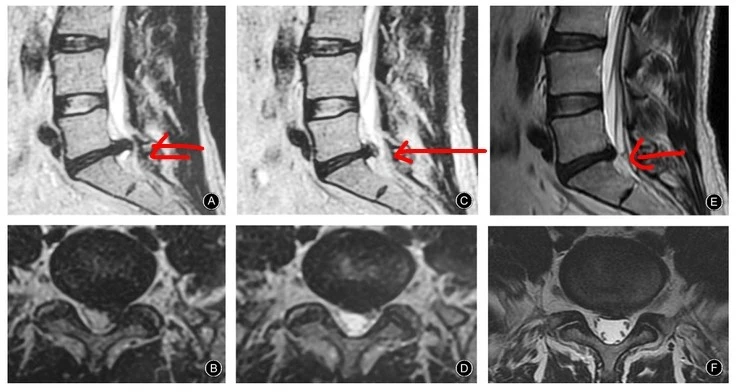

이 환자는 47세의 환자로 3일전에 삐끗하면서 아주 많은 양의 디스크가 탈출된 환자로 극심한 요통과 좌측 하지 방사통을 호소하던 환자였습니다. SLR은 좌측이 15도 우측이 70도 정도였지요. 그런데 한약을 복용하고 꾸준한 운동치료를 실시한 결과 2달이 지나자 (C, D) SLR은 70도 90도 회복되었고 일상생활이 가능해졌으며 어느 정도 디스크도 흡수되었습니다. 최종 MRI 재검사에서도 디스크가 완전히 흡수되었으며 정상적인 생활을 하게 되었습니다.